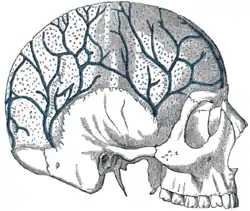

Diploic veins

The diploic veins are large, thin-walled valveless veins that channel in the diploë between the inner and outer layers of the cortical bone in the skull. They are lined by a single layer of endothelium supported by elastic tissue. They develop fully by the age of two years. The diploic veins drain this area into the dural venous sinuses. The four major trunks of the diploic veins found on each side of the head are frontal, anterior temporal, posterior temporal, and occipital diploic veins.[1]

Veins of the diploë as displayed by the removal of the outer table of the skull. | |

Types of diploic veins

The frontal, which opens into the supraorbital vein and the superior sagittal sinus.

The anterior temporal, which is confined chiefly to the frontal bone, and opens into the sphenoparietal sinus and into one of the deep temporal veins, through an aperture in the great wing of the sphenoid.

The posterior temporal, which is situated in the parietal bone, and ends in the transverse sinus, through an aperture at the mastoid angle of the parietal bone or through the mastoid foramen.

The occipital, the largest of the four, which is confined to the occipital bone, and opens either externally into the occipital vein, or internally into the transverse sinus or into the confluence of the sinuses (torcular Herophili).